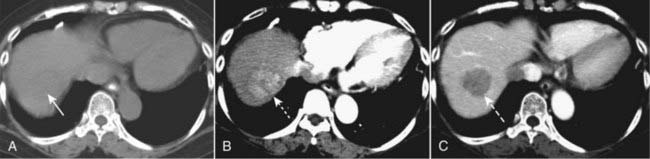

image CT evaluation of liver masses is usually done with a combination of scans obtained before and after intravenous contrast injection. Postcontrast scans are obtained in two phases: one is done quickly (hepatic-arterial phase) and a second is done about a minute later (portal-venous phase), the combination helping to best define and characterize liver masses. This combination of three separate scans done without contrast and then during the arterial phase followed by the venous phase is called a triple-phase scan (Fig. 18-26).

image

Figure 18-26 Triple-phase CT scan of the liver, hepatocellular carcinoma.

Evaluation of liver masses is usually done with a combination of scans including an unenhanced scan (A) and then two postcontrast scans: one obtained quickly (hepatic-arterial phase) (B) and a second (portal-venous phase) slightly delayed (C). The combination of three scans is called a triple-phase scan. This case shows the typical findings of a focal hepatocellular carcinoma. Most are low density (hypodense) or the same density as normal liver (isodense) without contrast (solid white arrow in A), enhance on the arterial phase with IV contrast (hyperdense) (dotted white arrow in B) and then return to hypodense or isodense on the venous phase (dashed white arrow in C).

image Recognizing hepatocellular carcinoma (HCC) on CT and MRI:

There are three patterns of presentation for hepatocellular carcinoma: solitary mass, large multiple nodules, diffuse infiltration throughout a segment, lobe or the entire liver (see Fig. 18-26).

On CT, most HCCs are low density (hypodense) or the same density as normal liver (isodense) without contrast, enhance on the arterial phase with IV contrast (hyperdense) and then return to hypodense or isodense on the venous phase (Fig. 18-32).

Figure 18-32 Diffuse hepatocellular carcinoma of the liver, CT.

There are three patterns of appearance for hepatocellular carcinoma: solitary mass (see Fig. 18-26), multiple nodules and diffuse infiltration throughout a segment, lobe (as in this case), or the entire liver. A, A typical low-attenuation lesion is seen in the right lobe of the liver on the nonenhanced scan (solid white arrow). B, The arterial phase demonstrates patchy enhancement (solid black arrow) indicating the probability of tumor necrosis in the low-attenuation areas. There is ascites present (A). The overall volume of the liver is decreased, and the contour is lobulated from underlying cirrhosis.